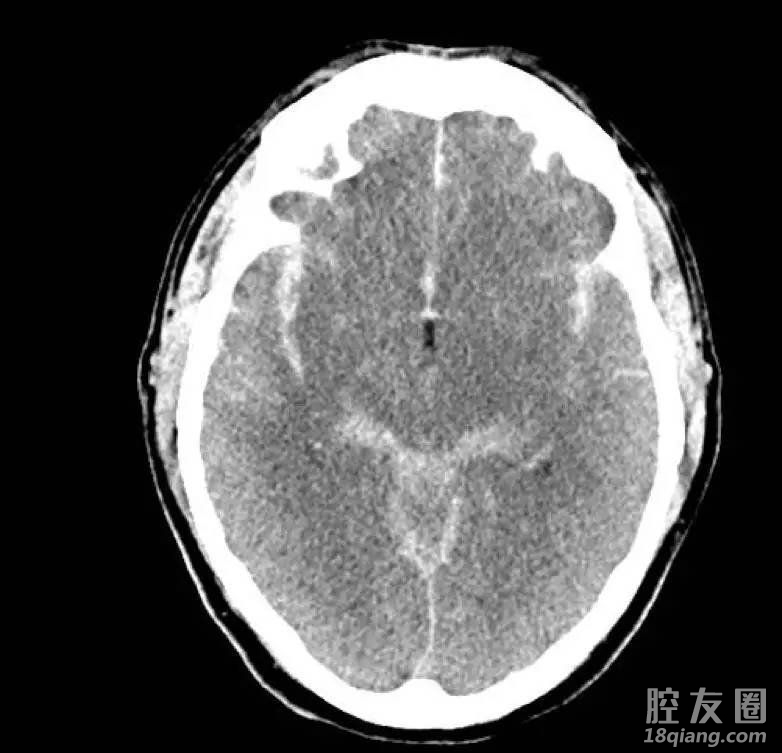

【为什么高血压会诱发脑出血?】

第一,血管是高血压的靶器官,血压居高不下可诱发动脉硬化,生成微型动脉瘤。高血压早期血管并不会出现器质性病变,但持续处于高压状态会造成动脉壁缺氧,引起营养不良和动脉内膜增厚,从而生成小动脉硬化。

第二,持续处于高压状态也会破坏动脉血管内膜完整性,降低血管壁弹性,一旦出现暴饮暴食、过度紧张和劳累以及情绪激动等就会导致血压升高,进而造成血管破裂。若是大脑中微小血管破裂出血,可造成头痛头晕、肢体麻木以及瘫痪;若是大血管破裂会使得出血量增加,造成意识障碍,生成脑疝,影响呼吸和心跳,进而威胁生命。